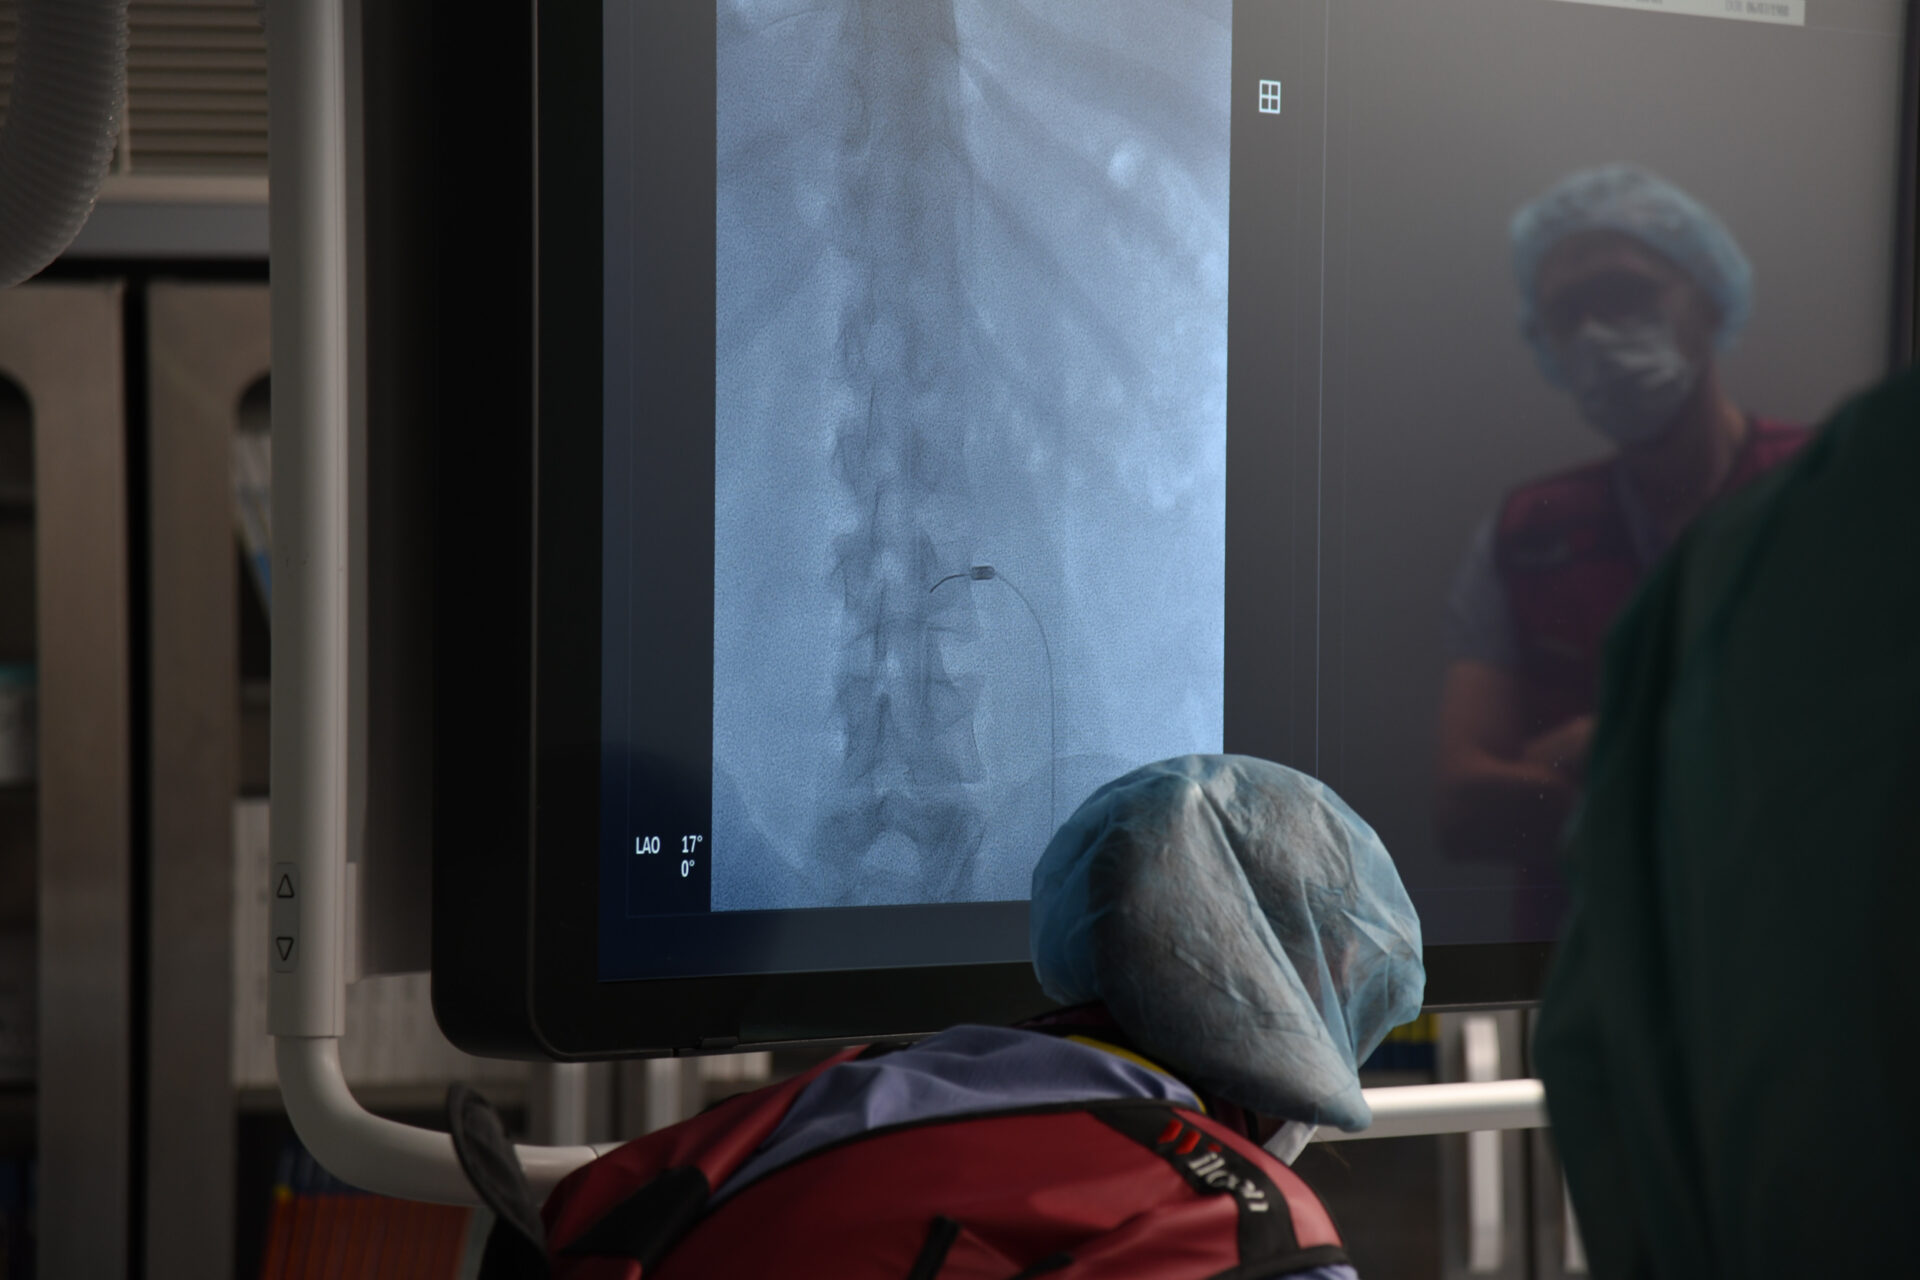

– Z przeciążenia stawów międzykręgowych. Co można wtedy zrobić? Zniszczyć unerwienie tych stawów. Robimy to wbijając igłę, pod kontrolą prześwietlenia rentgenowskiego, bo jest to metoda wymagająca precyzji. Do igły wprowadzamy emiter prądów wysokiej częstotliwości i nagrzewamy tkanki do temperatury – w tym konkretnym przypadku – 85 stopni Celsjusza. Nagrzewamy miejscowo tylko tę strukturę, która nas interesuje, bo pole rażenia tej elektrody jest niewielkie – tłumaczy lekarz.

Wysoki poziom wykonywania termolezji w słupskim szpitalu jest możliwy dzięki używanemu sprzętowi wysokiej klasy np. nowoczesnemu angiografowi zakupionemu przez szpital na początku 2025 r.